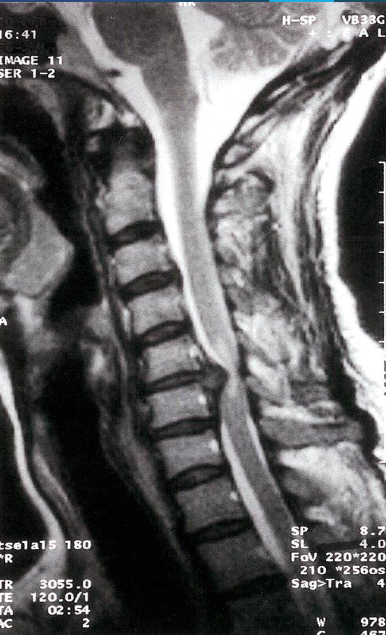

Cervical disk herniation

MRI cervical spine (T2-weighted; sagittal plane) of a

patient with symptoms of cervical myelopathy

A herniated disk at C5–6 effaces the dural sac and compresses the spinal cord. Hyperintense compression-induced edema is seen within the cord

Sagittal T2 MR - Syringomyelia

young adult women with optic neuritis

T2 -weighted MRI showing a plaque of demyelination (arrow) in a patient with multiple sclerosis